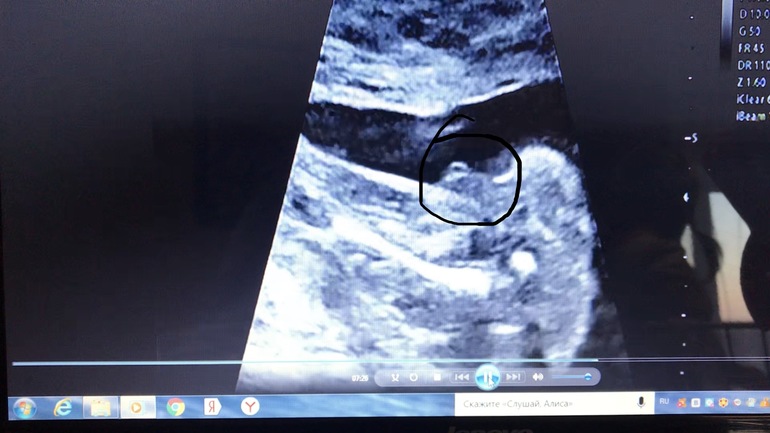

Пол малышаВчера ездили на второй скрининг.Срок 20недель 5 дней. Специально выбирала хорошего врача, чтобы все получше посмотрел. В целом все у нас отлично. В самом начале осмотра спросил-смотрим ли пол. Ну, я говорю, что мы мы знаем, т.к. НИПТ делали. Говорю, покажите папе))) А ребёнок у нас на попе сидит, голова вверху. Я понимаю, конечно, что не видно было и ножки поджал. Но... когда он сказал-девочка-я чуть с кушетки не упала. Муж побледнел))) Я говорю-какая девочка, мы НИПТ делали! У нас мальчик, две девочки уже есть))) Начал смотреть с другой стороны-извинился зачем-то, и минут 15 показывал нам типа мошонку и пенис...

С той стороны, когда он смотрел первый раз и увидел девочку- я тоже мальчугового ничего не нашла))) Да, потом вроде увидела. Дома сто раз пересмотрела диск, сделала фотки. Ведь мальчик?НИПТ же не ошибается?